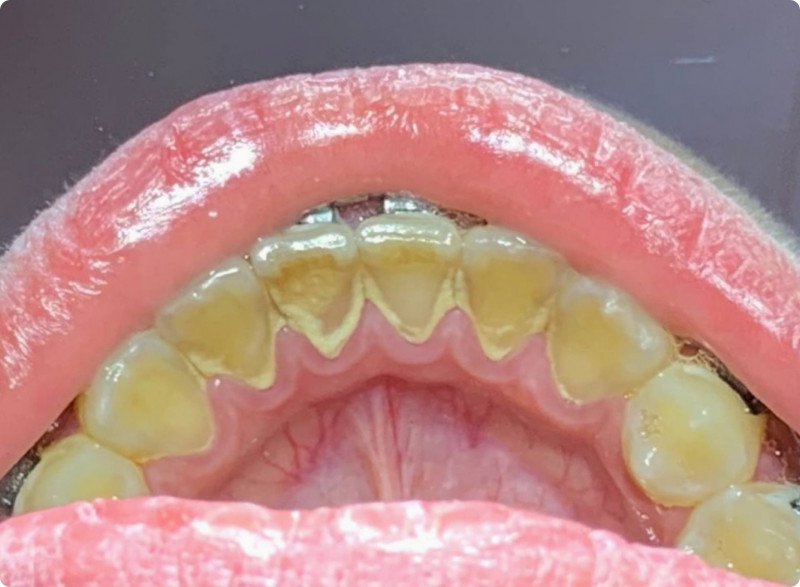

На странице представлено портфолио стоматологий Красноярска с работами до и после профессиональной чистки зубов. В нашем портфолио собраны разные клинические случаи: от удаления незначительного налета до снятия массивного поддесневого камня. Здесь вы можете увидеть, как возвращается естественный цвет и внешний вид зубов после процедуры. Изучите результаты до и после чистки зубов, чтобы увидеть реальный эффект и выбрать клинику в Красноярске, где профессиональная гигиена поможет вернуть зубам здоровый вид.

Профгигиена